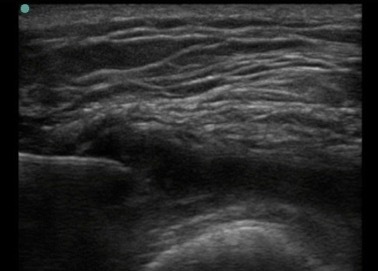

Knee Suprapatellar Recess Simple Effusion Image